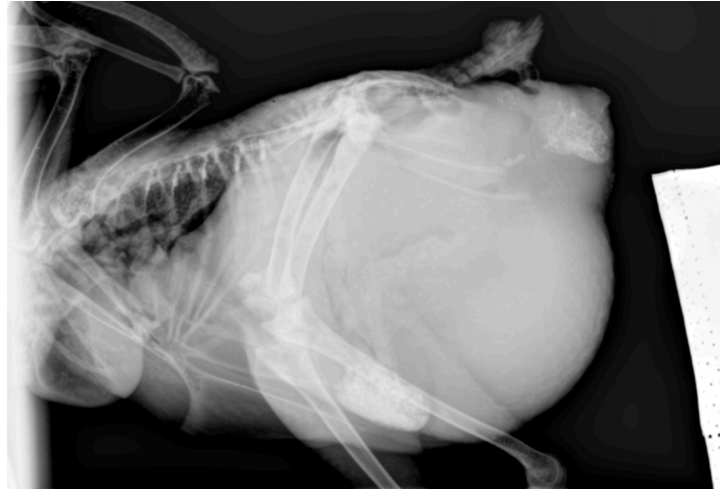

L'arrêt de la ponte peut être naturelle en hiver et certaines races sont aussi moins prolifiques que d'autres. Néanmoins, l'arrêt de la ponte peut également être un signe de maladie grave, telle qu'une rétention d'oeuf ou une impaction de l'oeuf dans le corps de la poule. Cela produit alors une infection de l'appareil reproducteur (une salpingite) ou des pontes ectopiques (ponte d'un oeuf à l'intérieur du corps). Le diagnostic fait souvent appel à des moyens d'imagerie (radiographie, échographie) et le traitement est généralement chirurgical avec une chirurgie coelomique de salpingectomie.